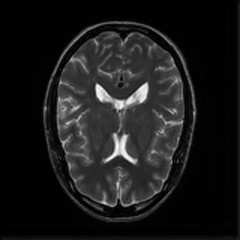

Limited by imaging systems, the reconstruction of Magnetic Resonance Imaging (MRI) images from partial measurement is essential to medical imaging research. Benefiting from the diverse and complementary information of multi-contrast MR images in different imaging modalities, multi-contrast Super-Resolution (SR) reconstruction is promising to yield SR images with higher quality. In the medical scenario, to fully visualize the lesion, radiologists are accustomed to zooming the MR images at arbitrary scales rather than using a fixed scale, as used by most MRI SR methods. In addition, existing multi-contrast MRI SR methods often require a fixed resolution for the reference image, which makes acquiring reference images difficult and imposes limitations on arbitrary scale SR tasks. To address these issues, we proposed an implicit neural representations based dual-arbitrary multi-contrast MRI super-resolution method, called Dual-ArbNet. First, we decouple the resolution of the target and reference images by a feature encoder, enabling the network to input target and reference images at arbitrary scales. Then, an implicit fusion decoder fuses the multi-contrast features and uses an Implicit Decoding Function~(IDF) to obtain the final MRI SR results. Furthermore, we introduce a curriculum learning strategy to train our network, which improves the generalization and performance of our Dual-ArbNet. Extensive experiments in two public MRI datasets demonstrate that our method outperforms state-of-the-art approaches under different scale factors and has great potential in clinical practice.